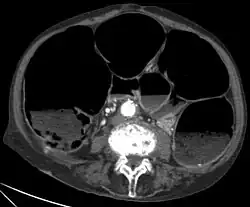

AxialeRekonstruktion eines CT-Scans des Abdomens einer älteren Frau mit einem Ogilvie-Syndrom (Pseudoobstruktion des Dickdarmes)

Die Diagnostik der Erkrankung ist einfach, da das Röntgenbild sehr charakteristische Zeichen aufweist. Der gesamte Dickdarm ist breit mit Luft gefüllt, vor allem der aufsteigende Teil des Dickdarmes erreicht eine Breite von oft mehr als 10 cm.